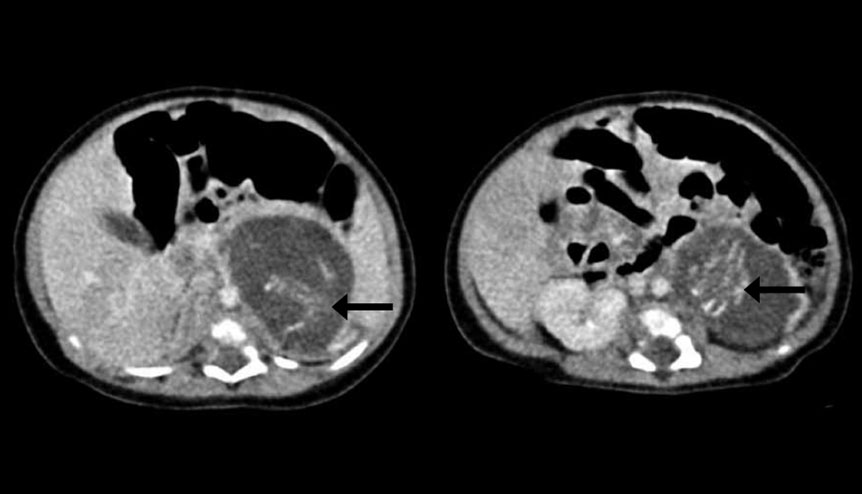

Os fetos removidos do corpo da bebé tinham 10 semanas de gestação, possuindo pernas, braços, espinal medula, a caixa das costelas, intestinos, órgãos genitais ambíguos e tecido cerebral primitivo. Estariam também ambos cobertos por pele e cada qual tinha o seu cordão umbilical, ambos ligados a uma placenta. Um deles pesaria 14,2 gramas e o outro 9,3 gramas.

A menina nasceu no Hospital Queen Elizabeth, em Hong Kong, de pais chineses com uma condição denominada como Fetos em feto que tem uma ocorrência de um para 500 mil nascimentos. Só foram reportados cerca de 200 casos em todo o mundo, o que dá para perceber a raridade da situação.